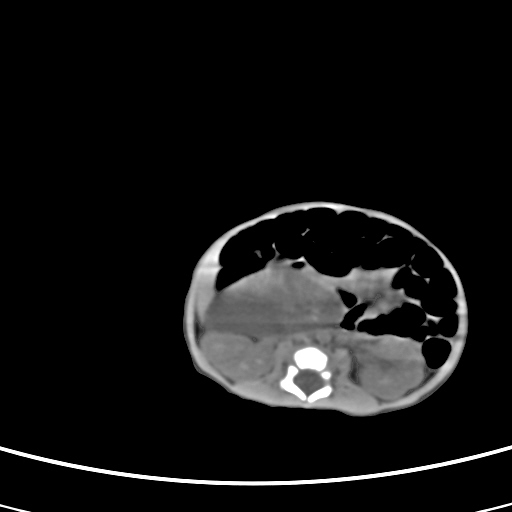

患儿,男性,出生后2天,在胎儿时b超已发现病变,患儿一般情况可。因病变部位偏向于右侧肾上腺区,目前考虑为神经母细胞瘤,不知各位能否支持。

反对定位在右肾上腺区的说法,那么神经母细胞瘤也可以暂时不予考虑。请看下图:

下面这幅图中,似乎可以见到肿瘤的薄包膜,其后与右肾之间的又是什么东西呢?这关系到肿瘤的定位、定性。我考虑病灶是位于肝十二指肠韧带内的畸胎瘤可能性比较大。请各位老师仔细看一下:

病灶巨大,位于右侧肾上腺区,与周围组织分界欠清,内见不规则钙化影,无明显脂肪组织,首先考虑神经母细胞瘤,但畸胎瘤不能排除。

手术结果为畸胎瘤